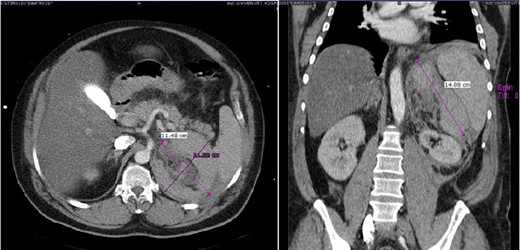

A 47-year-old male presented with, epigastric pain radiating to the back and profuse sweating. The patient was a smoker, obese and not on regular medication. Other than hypertension (BP: 210/120 mmHg), observations were normal. The abdomen was distended without rebound tenderness. Blood tests showed leukocytosis (WBC:12.000, 55% neutrophils), while hematocrit, platelets, coagulation profile and routine biochemistry were normal. Ultrasonography (US) was unremarkable, while computed tomography (CT) revealed a large retroperitoneal hematoma at the site of the left adrenal gland, with minimal contrast extravasation (Fig. 1). The patient was transferred to ICU, due to uncontrolled hypertension and suspicion of underlying pheochromocytoma, despite no obvious CT finding. The patient became hemodynamically unstable and Hct dropped to 35%. Angiography that followed showed no contrast extravasation. Further reduction of Hct to 22% necessitated transfusion with 2 units of blood. Subsequent CT showed stable hematoma without active bleeding. The patient was transferred to the ward after 8 days. Investigation for potential adrenal mass and post-hemorrhage adrenal insufficiency was commenced, requiring restricted diet for testing of urine vanillylmandelic acid (VMA). Blood cortisol and ACTH were normal, while investigation for exclusion of pheochromocytoma was inconclusive. Metaiodobenzylguanidine (MIBG) scan was negative. The patient was discharged with well-controlled blood pressure. On follow-up, urine VMA was reduced, while abdominal MRI, performed after 2 months, showed complete hematoma resolution and no underlying mass (Fig. 2).

Case 1 presenting imaging (CT) showing a large left peri-adrenal hematoma.